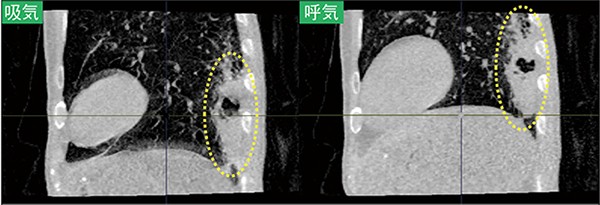

呼吸ダイナミックCTが特に威力を発揮する胸部疾患として、(1) 中枢気道の異常および奇異性運動の可視化(小児の先天性気道狭窄等)、(2) 胸部腫瘍の周囲臓器への癒着・浸潤の評価(肺がんの大動脈浸潤等)、(3) 慢性閉塞性肺疾患(COPD)や喘息等の閉塞性呼吸障害における気道・肺運動の評価などが挙げられる。聖マリアンナ医科大学でしばしば撮影される、小児の先天性中枢気道異常の呼吸ダイナミックCTでは、従来は喉頭ファイバーや気管支鏡でのみ観察可能であった、種々の異常な現象・呼吸性運動が確認されている。また、最もわかりやすく呼吸ダイナミックCTの有用性が示される領域としては、肺がんなどの悪性腫瘍が周囲の構造物へ癒着・浸潤しているか判定できることである。これはACTIve Study Group参加施設のみならず、多くの施設ですでに試みられているが、対象とする肺がん・縦隔内腫瘍などを深呼吸下に呼吸ダイナミックCTで撮影することで、周囲構造物へ癒着・浸潤がある場合には“腫瘍がすべらない”、癒着・浸潤がない場合には“腫瘍がすべる”ように見える点を活用するものである3)。単に悪性腫瘍のステージングのみならず、執刀医に対し術前に癒着・浸潤に関する正確な情報提供・注意喚起を可能にする点で有用性が高い(図1)。この呼吸ダイナミックCTを用いた胸部腫瘍の周囲癒着・浸潤は、例えば肺がんが大動脈に浸潤しているかどうかといった、場合によっては手術の適否自体を左右するような局面でも威力を発揮する。

図1 肺がんの呼吸ダイナミックCT(抜粋)

吸気から呼気で胸膜直下の大きな肺がん(黄破線)が胸壁直下を滑るように移動しており、壁側胸膜への癒着や浸潤が存在しないことがわかる。